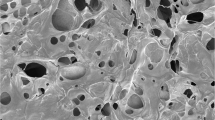

The use of decellularized extracellular matrix as a biomaterial has gained significant attention in tissue engineering and regenerative medicine due to its ability to accurately mimic the natural cellular environment. Based on our previous attempt to induce regeneration using kidney hydrogels, we were inclined to use them to produce a unique composition that may promote nerve regeneration. Initially, the kidney-derived dECM hydrogel was prepared with concentrations of 8 mg/ml and 16 mg/ml (Fig. 1a). The scanning electron microscope (SEM) images revealed that these hydrogels possessed a fibrous morphology with a microporous structure (Fig. 1b). This structure, as previously discussed 41, is conducive to cell infiltration and nutrient permeation. To evaluate the potential beneficial effects of dECM hydrogel as a scaffold in neuronal regeneration, we assessed their impact on neurite outgrowth using DRG (Fig. 1c). Significant axonal growth was observed on Day 5, as confirmed via immunohistochemical analyses using anti-β-III tubulin antibodies. DRG-derived β-III tubulin-positive axons showed considerable elongation on the 8 mg/ml dECM hydrogel compared with the 3 mg/ml collagen I and 16 mg/ml dECM hydrogel (p = 0.047) (Fig. 1d,e). Specifically, the average neurite length was 883.93 ± 61.01 μm on collagen I, 1107.40 ± 39.96 μm on the 8 mg/ml decellularized kidney hydrogel, and 963.80 ± 29.99 μm on the 16 mg/ml dECM hydrogel. Furthermore, these findings suggest that the 8 mg/ml dECM hydrogel provides an optimal microenvironment for promoting neurite extension, making it a promising scaffold for neural tissue engineering applications.

Preparation and characterization of dECM hydrogels and effect of dECM hydrogel substrates on DRG neurite growth. (a) Diagram of the preparation process for kidney-derived dECM hydrogel. (b) SEM images of decellularized kidney hydrogel (8 mg/ml). Scale bar: 5 μm. (c) Experimental design and images of DRG culture on dECM hydrogel. (d) Tuj1-positive DRG neurites visualized using fluorescently stained images on different hydrogels. Scale bar: 200 μm. (e) Quantification of the neurite length of DRG on collagen I (n = 3) and dECM hydrogel (8 mg/ml (n = 4) and 16 mg/ml (n = 3)). One-way ANOVA followed by the Tukey–Kramer test; N.S., not significant; *P < 0.05. Data are expressed as mean ± SEM.